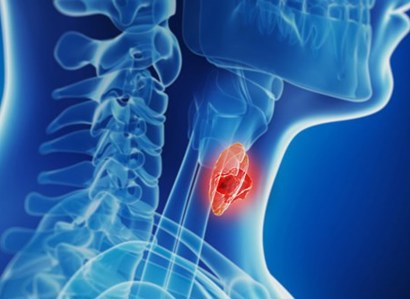

The thyroid is a small butterfly-shaped gland inside the neck. Medical issues are treated as part of endocrinology.

Read Thyroid gland issues Article